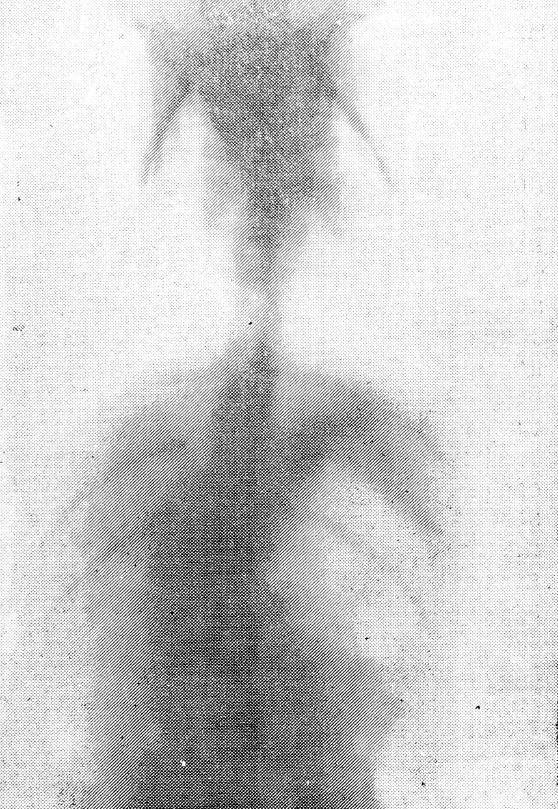

В подопытной группе через 1,5 месяца по мере роста животного образовалось С-образное боковое искривление с вершиной на уровне оперативного вмешательства, направленной в здоровую сторону. Средняя величина искривления составляла от 15 до 17° у всех подопытных животных без исключения (рис. 2). Через 3 месяца имело место дальнейшее прогрессирование бокового искривления до 26—28°. Регрессии ни в одном случае не произошло.

Рис. 2. Спондилография грудного отдела позвоночника через 1,5 месяца после операции. С-образный сколиоз I степени